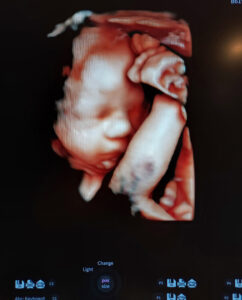

Can’t Wait To Meet Him

We are counting down the weeks until we meet our son! Our surgery was on 2/7/2022, his due date is April 11th 2023.

We are so in love with him!

Thank you for making this possible, Dr Monteith!